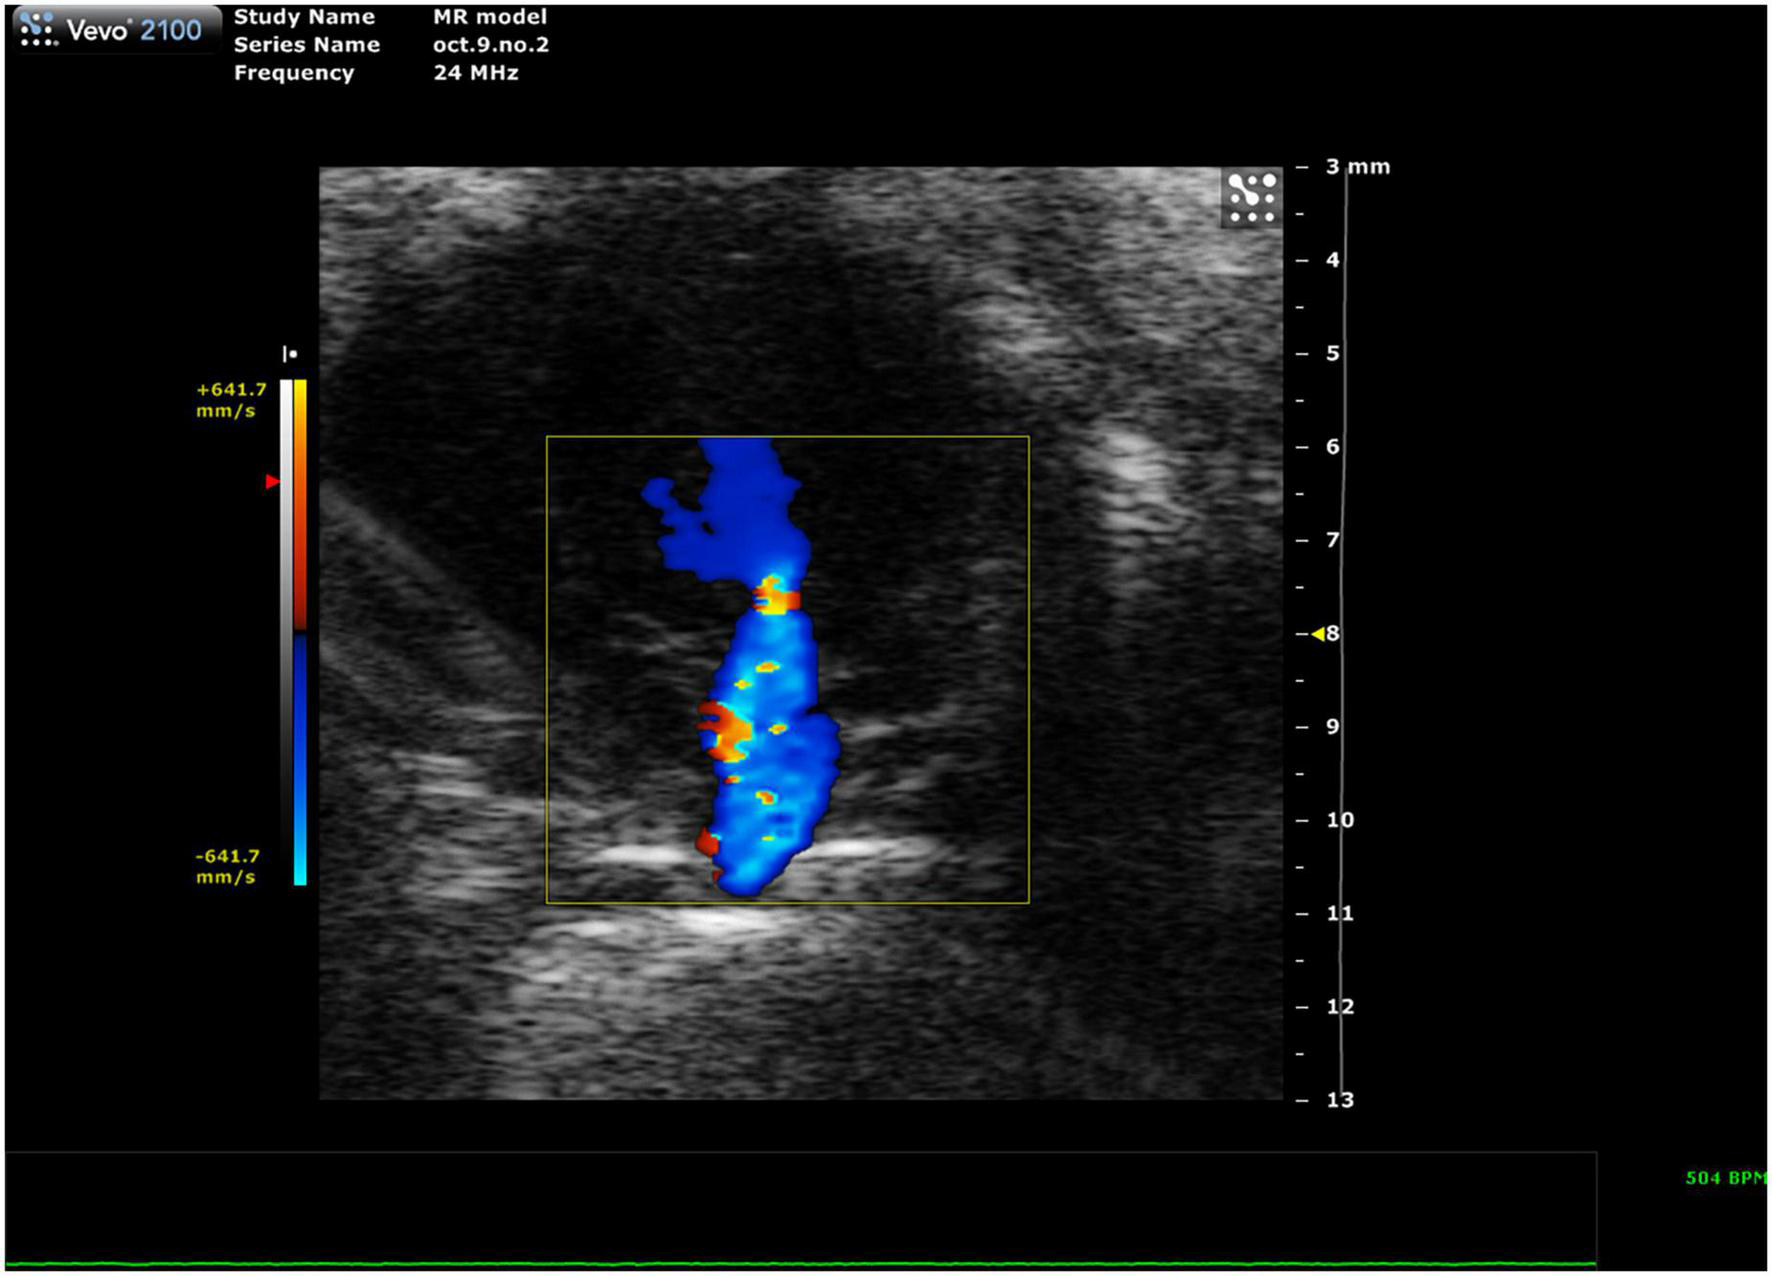

2.3.3.1 Mitral regurgitation

Mitral regurgitation (MR) has not been well-described in mice because of their resistance to developing mitral valve prolapse (11). However, Li et al. recently reported the first mouse model of severe MR (Figure 11, 12). To continue development of mouse models of MR, it is important to be able to recognize the presence of mitral regurgitation, which appears as a mixed color pattern of systolic backflow from the LV to the LA on PSAX Color Doppler.

FIGURE 11

Representative image showing a mixed color pattern of systolic backflow from the left ventricle to the left atrium in severe mitral regurgitation.